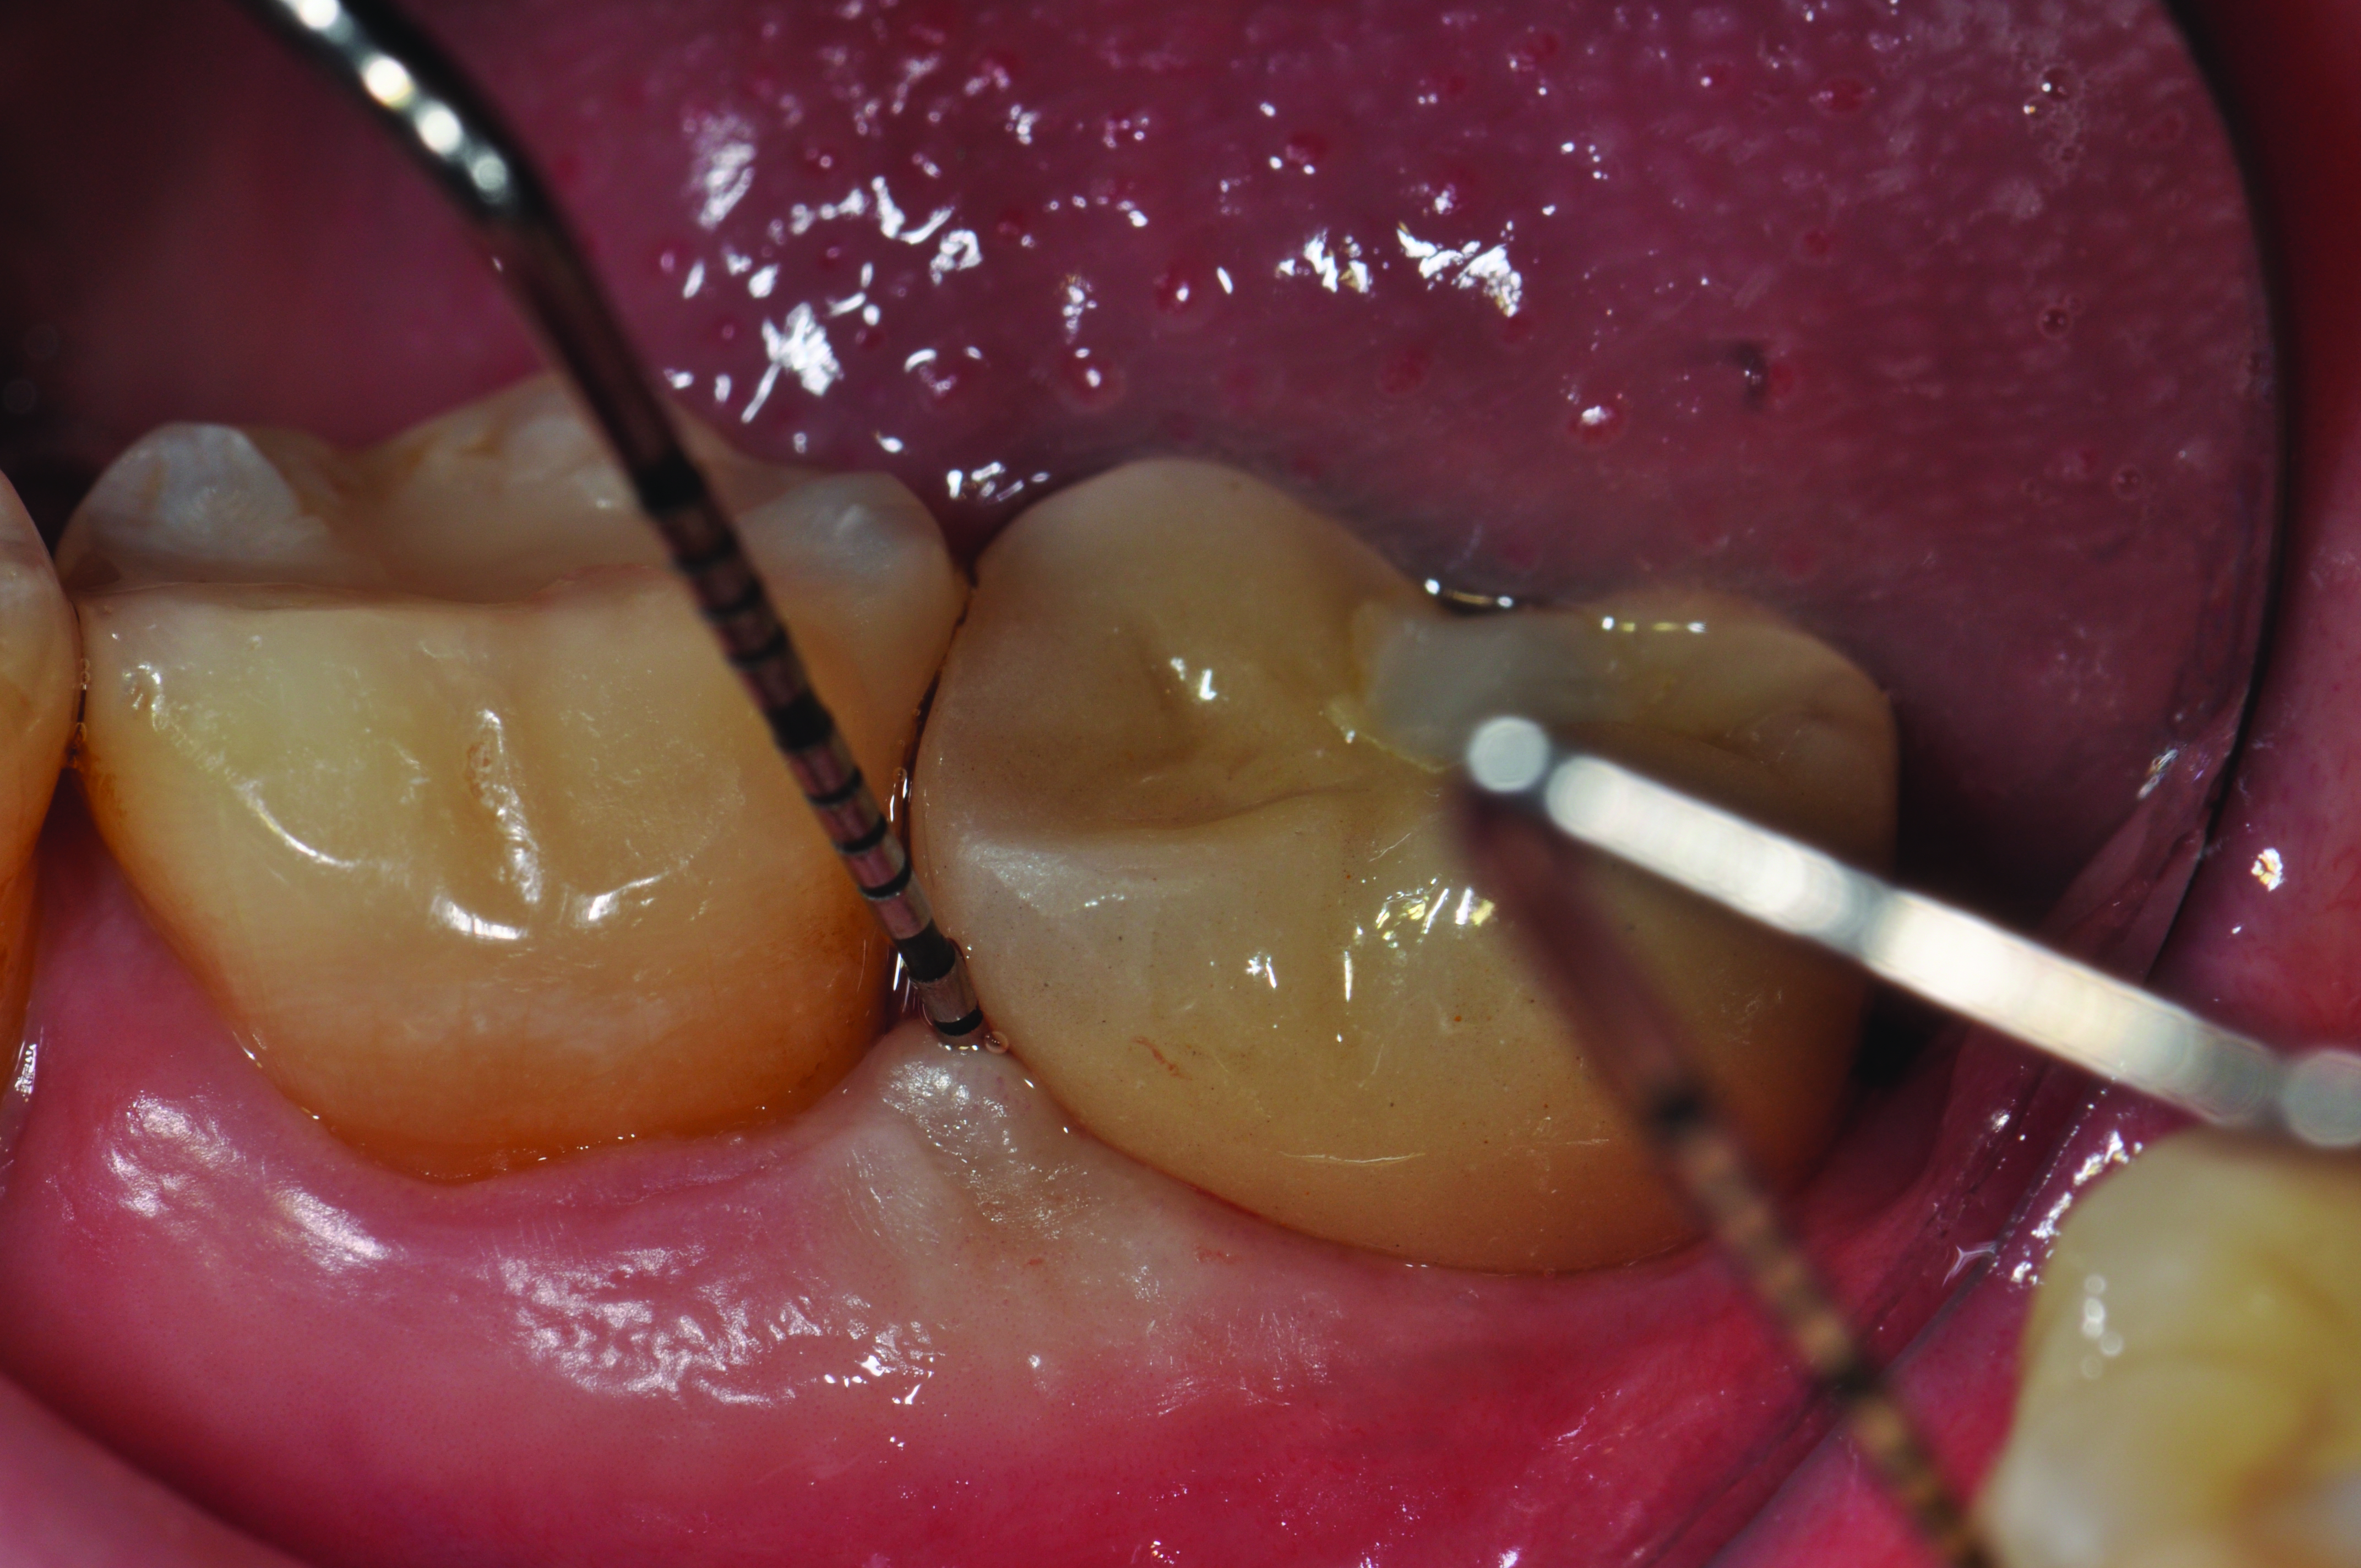

Clinical view of this area suggests that peri-implant mucositis is present, as there is bleeding on light probing and inflammation of the tissue.

Figure 6

Four weeks following nonsurgical treatment, the area is healthy as probing depths are now shallow and bleeding is absent. Treatment involved scaling of the area, which removed all plaque and a slight amount of cement, and irrigation with an anti-inflammatory hydrogel.

Figure 7